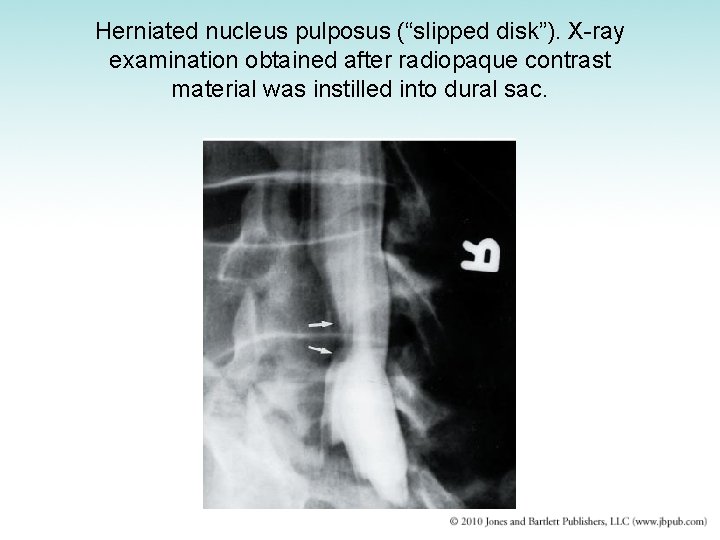

Intervertebral Disk Disease • Intervertebral disks undergo progressive wear -and-tear degeneration of both nucleus and annulus • Nucleus pulposus may be extruded through tear in annulus fibrosus • Manifestation – Sudden onset of back pain radiating down the leg • Diagnosis: CT scan or myelogram • Treatment: surgery

Herniated nucleus pulposus (“slipped disk”). X-ray examination obtained after radiopaque contrast material was instilled into dural sac.